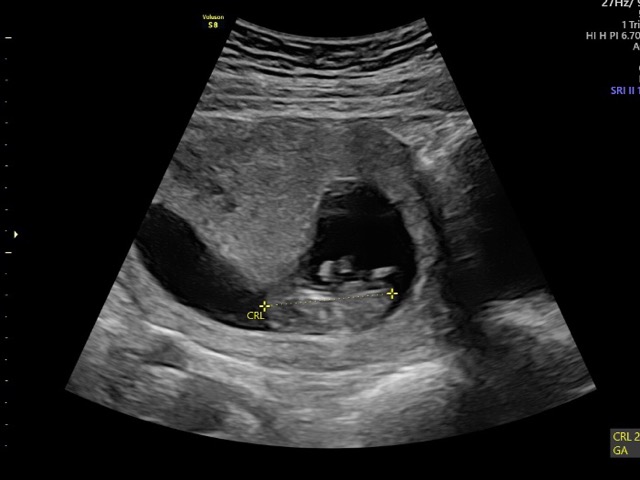

Reassurance scan done ✅ so relieved.. RAMZI THEORY.. what do we think?